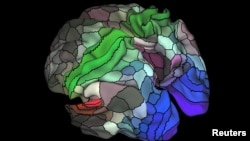

Using MRI images from the brains of 210 people, the researchers said on Wednesday they were able to pinpoint 180 distinct areas in the cerebral cortex, the brain's thin, wrinkly outermost layer made of so-called gray matter.

These areas were present in both the left and right hemispheres of the cerebral cortex. More than half, 97 of them, were previously unknown. The researchers nailed down the specific function of some of the areas, but said they were only scratching the surface on understanding what all of the areas did.

The map could assist in the study of brain maladies such as autism, schizophrenia, dementia and epilepsy, and shed light on the differences between the brains of people with such conditions and healthy people, the researchers said.

Neuroscientist Matthew Glasser of Washington University in St. Louis, lead author of the study published in the journal Nature, said the map also may be useful in neurosurgery, helping surgeons avoid damaging important brain areas involved in speech or movement.

"We consider this to be the most accurate and detailed map of human cerebral cortex published to date," Washington University neuroscientist David Van Essen said.